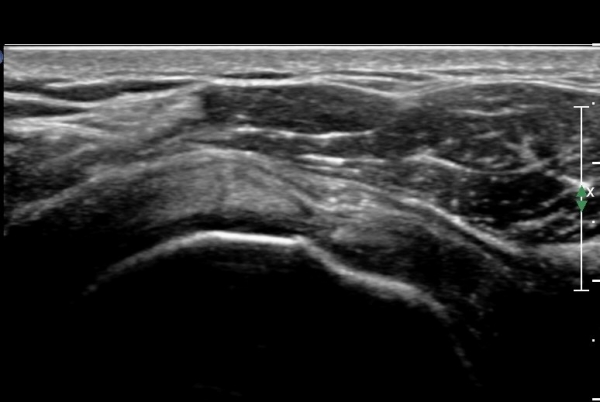

¿À±¸µ¹±â°ßºÀÀδë Á¾´Ü¸é°Ë»ç¿¡¼­ ÀÎ´ë ½ÉÃþ¿¡ ¼ö¾×Àú·ù°¡ °üÂûµÊ(»çÁø 1, 2)

ÀÌ´Â Ãæµ¹ÁõÈıºÀ» ¾Ï½ÃÇÏ´Â ¼Ò°ßÀÓ.